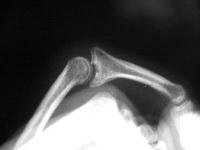

First impression was that the palmar fragment was probably big enough to take down and reinsert. However, comparison of films shortly after the fracture (above) and at two months (below) confirms the injury as a healed comminuted central impaction fracture with splay and hinging of the volar cortex.